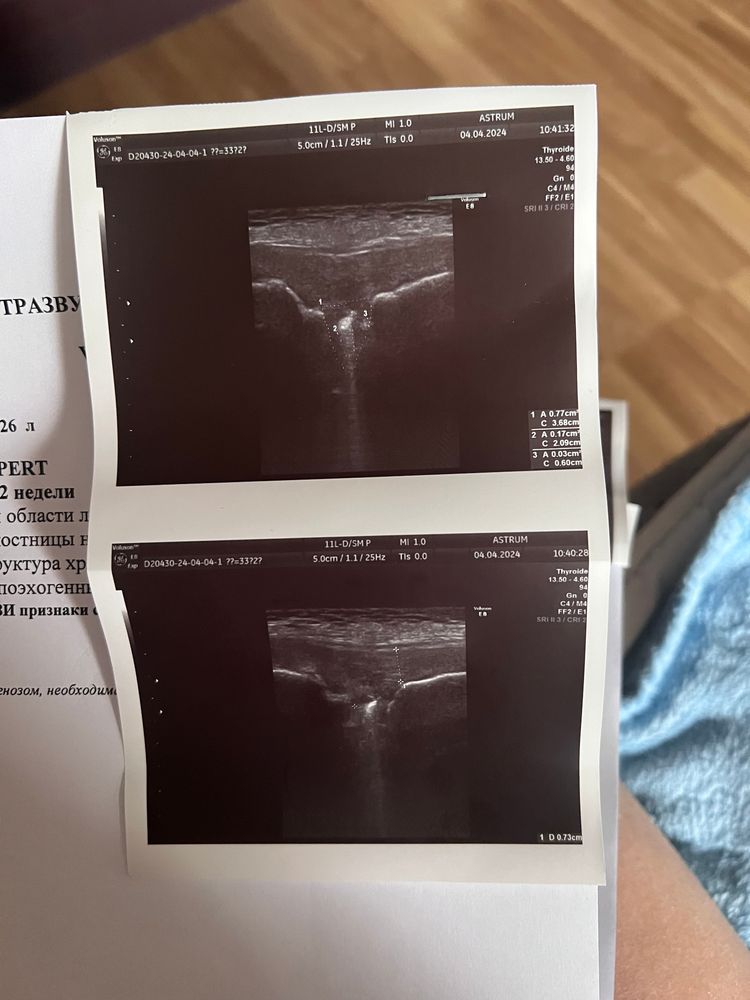

Была на узи, попросила дополнительно посмотреть симфизит(уже больше месяца больно ноги поднимать лежа, да и ходить долго не могу). Моя гиня лишь мило улыбается, мол что ты хочешь, у всех так. Срок то же 33 недели.

и вот сегодня сходила, врач сказала что есть что-то не опасное, но по результатам не понять. В интернете пишут про расхождение в см, а у меня в процентах. Может кто сталкивался?

Расхождение более 10 мм показание к КС. У вас меньше. Поэтому делать ничего не нужно, пройдет после родов.